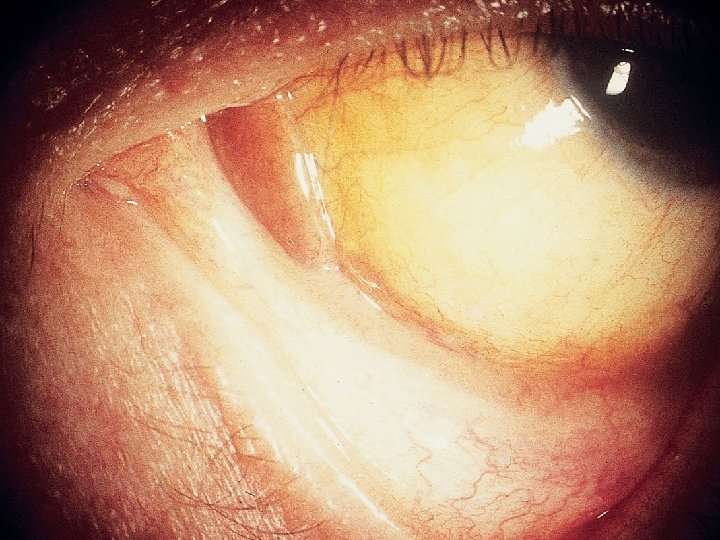

Retinal Toxoplasmosis

CMV • Typically does not cause disease until CD 4 <50 • Manifestations in HIV patients: – Retinitis • Unilateral or bilateral visual disturbance • Confirmed by retina exam showing “scrambled eggs & ketchup” (exudates & hemorrhages) – GI disease • Esophagitis • Colitis with watery diarrhea, abdominal pain • Neurologic disorders